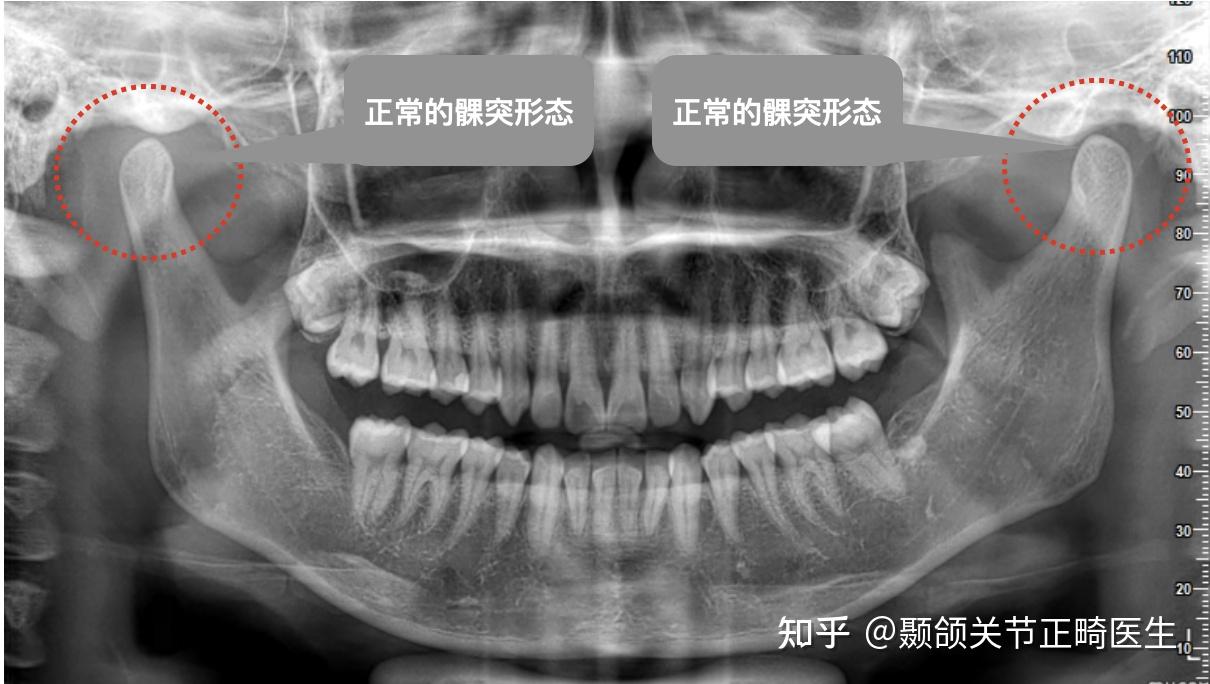

头颅正侧位,三维ct,双侧颞下颌关节的影像资料

图片尺寸2667x2000

本张照片显示tmj界面,对称性观察双侧颞下颌关节

图片尺寸1600x1200